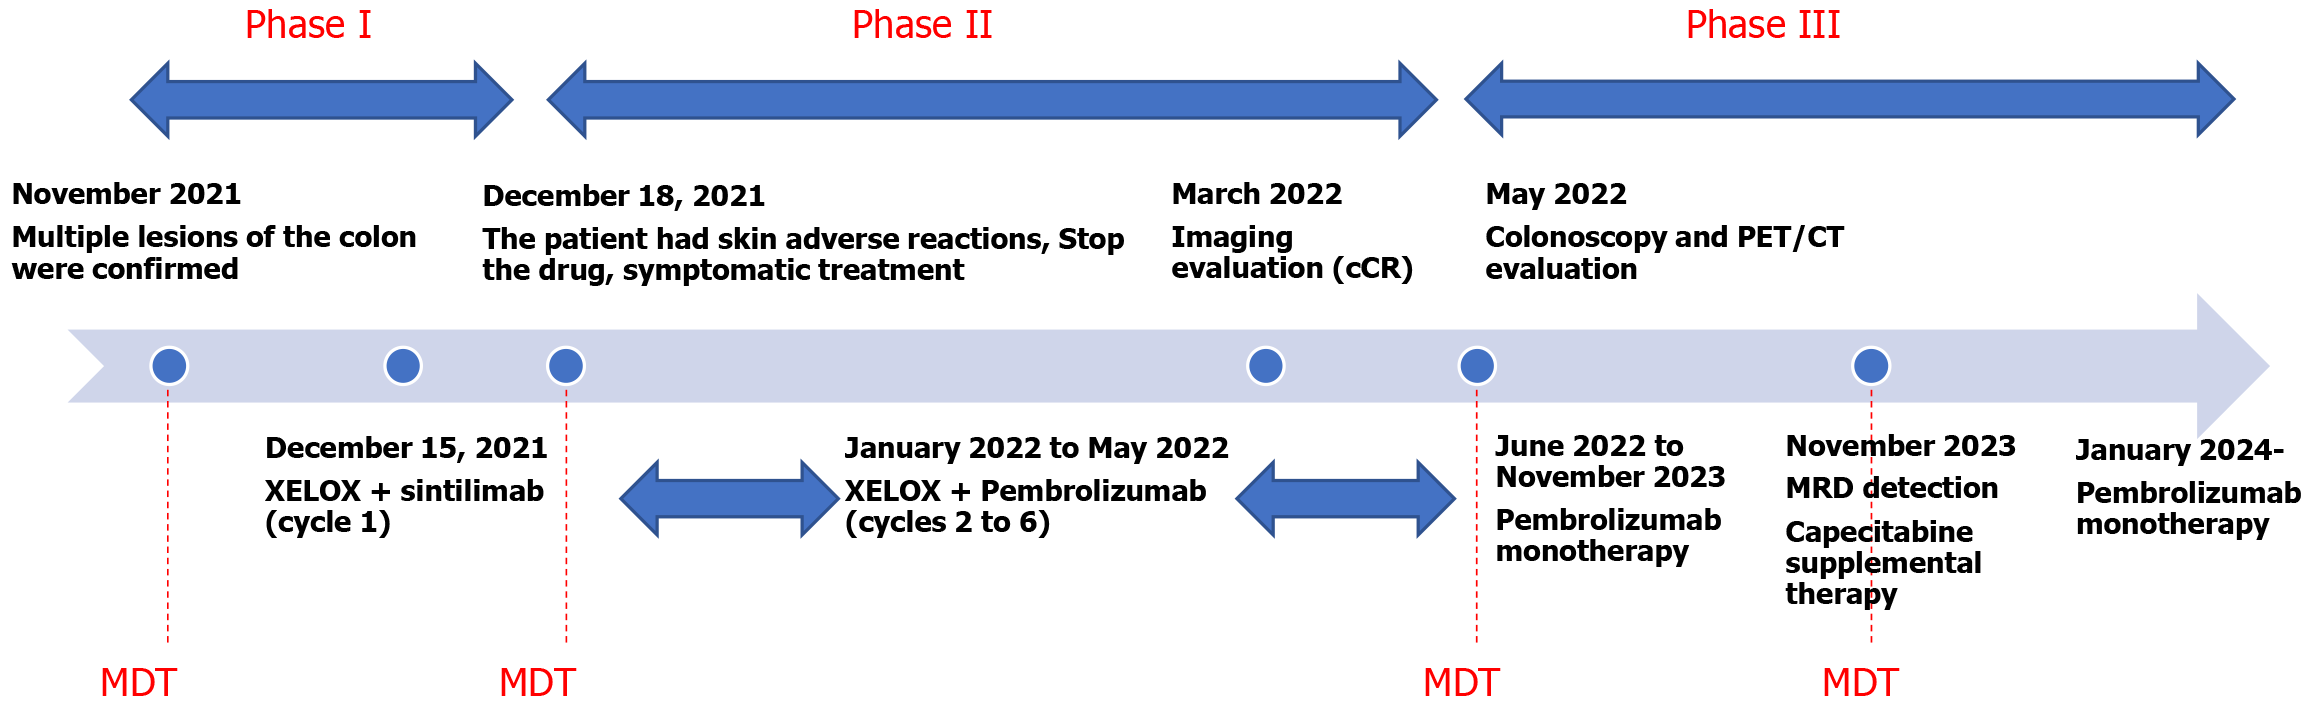

The treatment strategy was anchored in precision medicine, encompassing a tailored combination of chemotherapy, immunotherapy with programmed death protein 1 (PD-1) inhibitors, and rigorous molecular surveillance. The chemotherapy regimen consisted of oxaliplatin (130 mg/m2 intravenously on day 1) and capecitabine (1000 mg/m2 orally twice daily from day 1 to day 14), repeated every 3 weeks. For immunotherapy, the initial PD-1 inhibitor sintilimab was administered every 3 weeks, starting on December 15, 2021. However, due to a drug-induced rash, sintilimab was discontinued after the first cycle, and pembrolizumab was used for subsequent cycles from January 2022. Starting in 2024, the dosing interval of pembrolizumab was changed to every 2 months for maintenance therapy (Figure 3). Additionally, the patient took anti-emetics (metoclopramide tablets or ondansetron tablets as needed) during follow-up. No other medications were used.

The patient’s sustained complete clinical response for over 30 months is a testament to the efficacy of this synergistic treatment approach. This case illustrates the importance of a comprehensive, personalized strategy that combines chemotherapy, immunotherapy, targeted therapy, genetic counseling, and rigorous monitoring. It sets a new standard for the care of patients with CRC induced by LS, demonstrating the potential of a synergistic approach to achieve superior outcomes in the management of this complex condition (Figure 3).